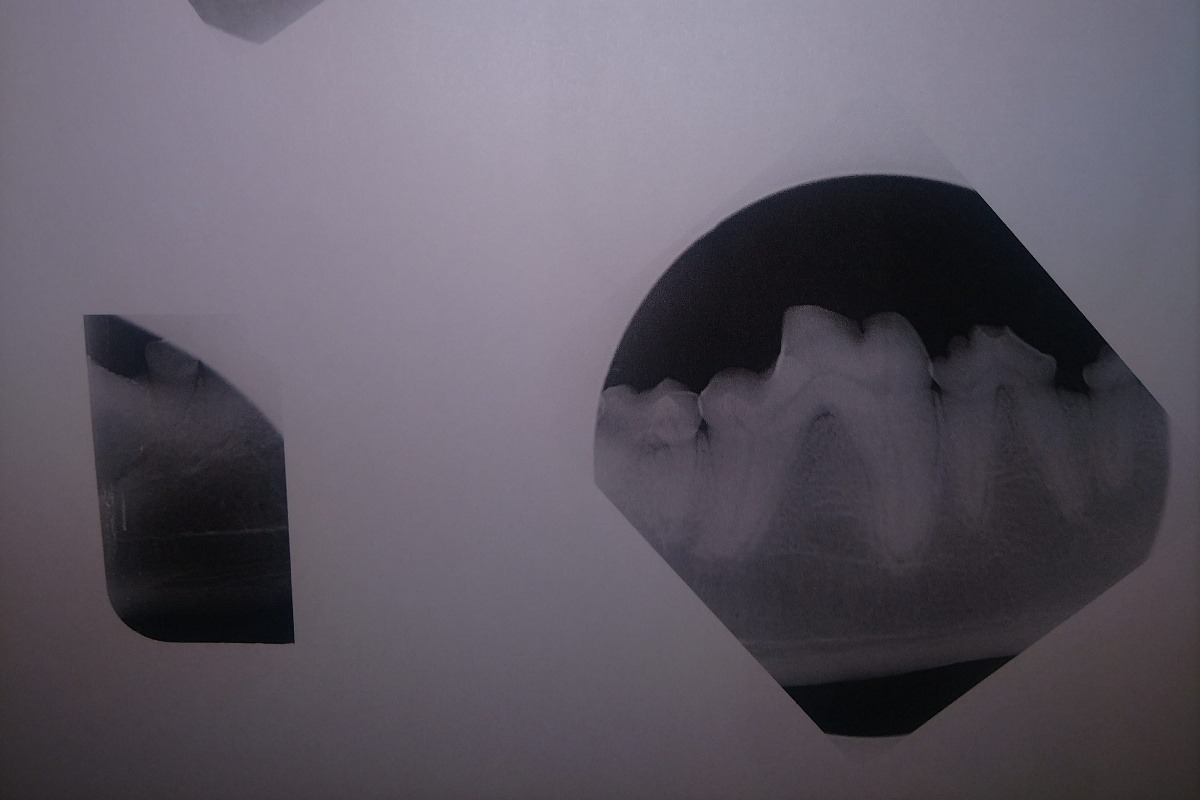

The radiographs laid out a dim story of that long term damage: all 4 canine teeth were dead, 2 of those canines were broken off from the recent attempt on the gate; all of her lower incisors, and several molars on each side were also dead. The vet was surprised, in spite of massively evident wear and tear, that her upper incisors appeared to still be alive. More of her teeth were dead than live. However, there was some good news in that her gums were completely free of gum disease, she had very little plaque and tartar buildup, and that she hadn't lost any of the bone her teeth were seated in.

The following photos are her radiographs for anyone that knows how to read them, so you can see all the dead teeth that need future extractions, and some show the root canals: